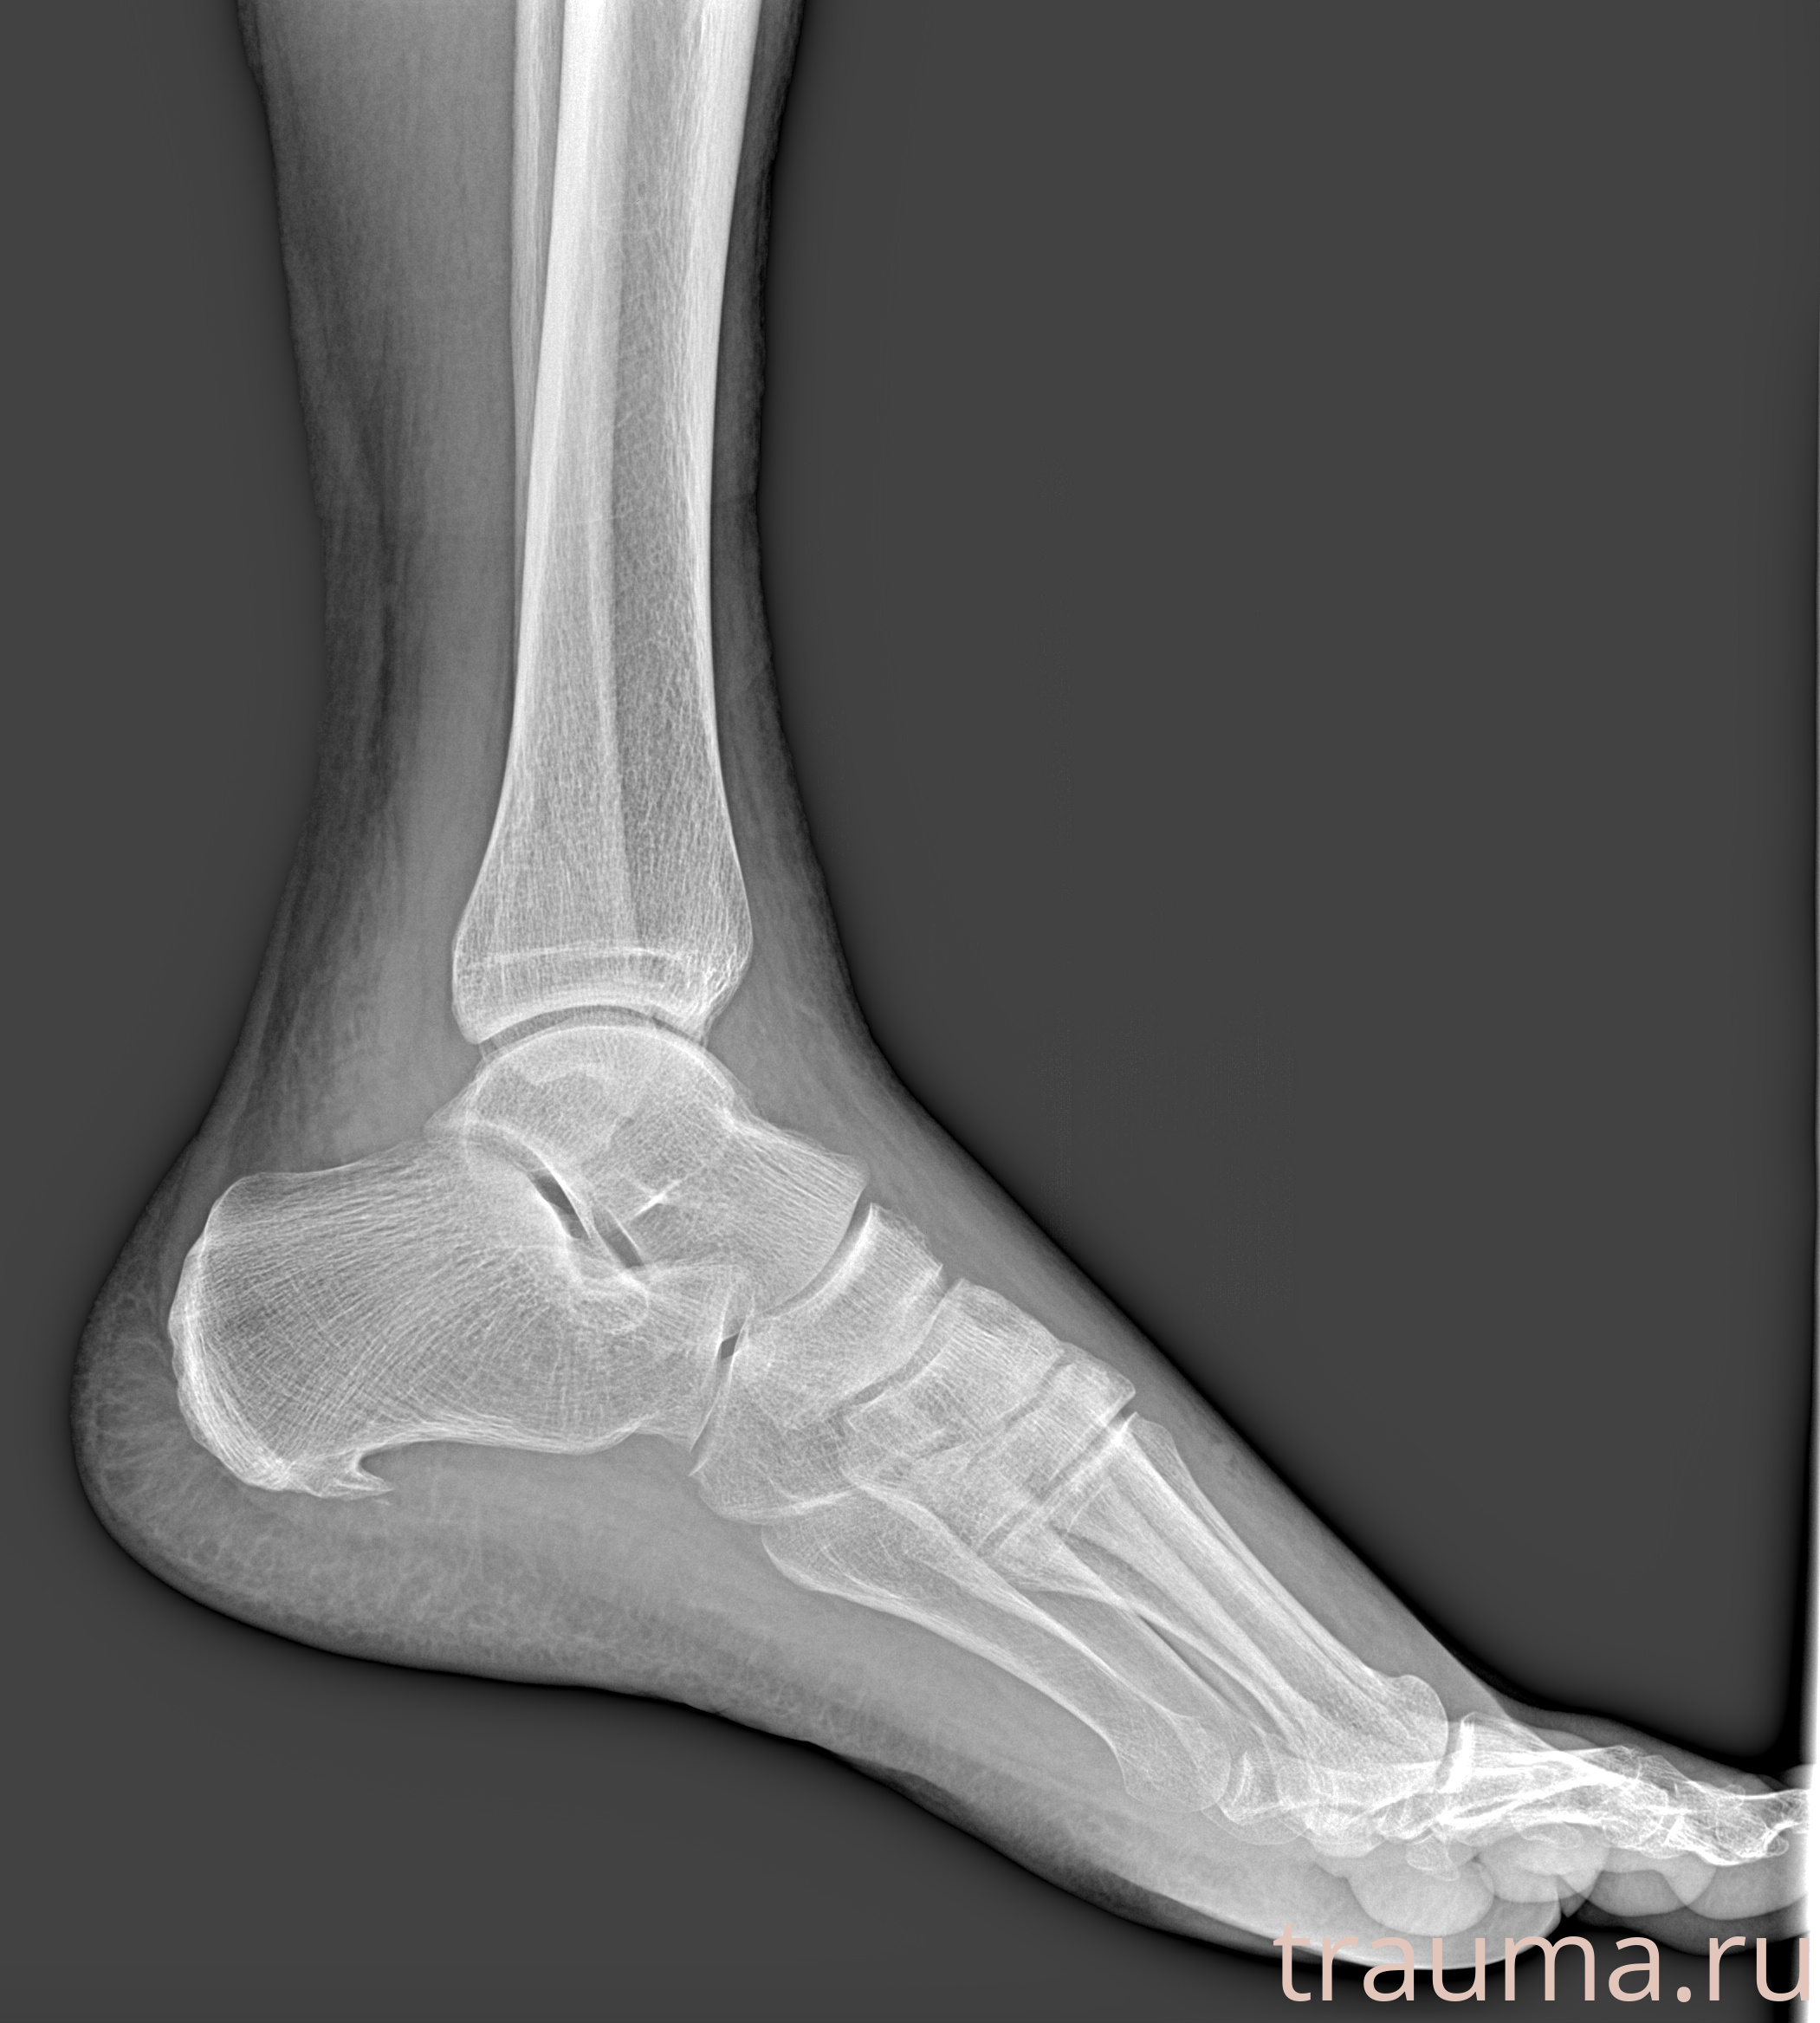

Рентгенограммы

Рентген на дому: по вашему адресу приезжает врач-рентгенолог, травматолог-ортопед с мобильным рентгеновским аппаратом, проводит диагностику травмы или заболевания, делает необходимые рентгенограммы, дает рекомендации по дальнейшему лечению. Получить качественные снимки в домашних условиях возможно благодаря уникальной методике, разработанной МосРентген Центром для института  Склифосовского

Яркость: 1   Контраст: 1   Инвертировать: 0 Увеличение: 1

Перетаскивайте мышь вверх/вниз для контраста, влево/право для яркости. Прокрутка колесом изменяет масштаб. Нажмите Сбросить для возврата к исходному изображению. При увеличении держите мышь в той области, которую хотите рассмотреть.